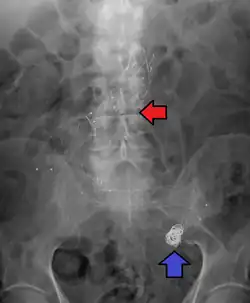

Abdominal aortic aneurysm involves a regional dilation of the aorta and is diagnosed using ultrasonography, computed tomography, or magnetic resonance imaging. A segment of the aorta that is found to be greater than 50% larger than that of a healthy individual of the same sex and age is considered aneurysmal.[9] Abdominal aneurysms are usually asymptomatic but in rare cases can cause lower back pain or lower limb ischemia.